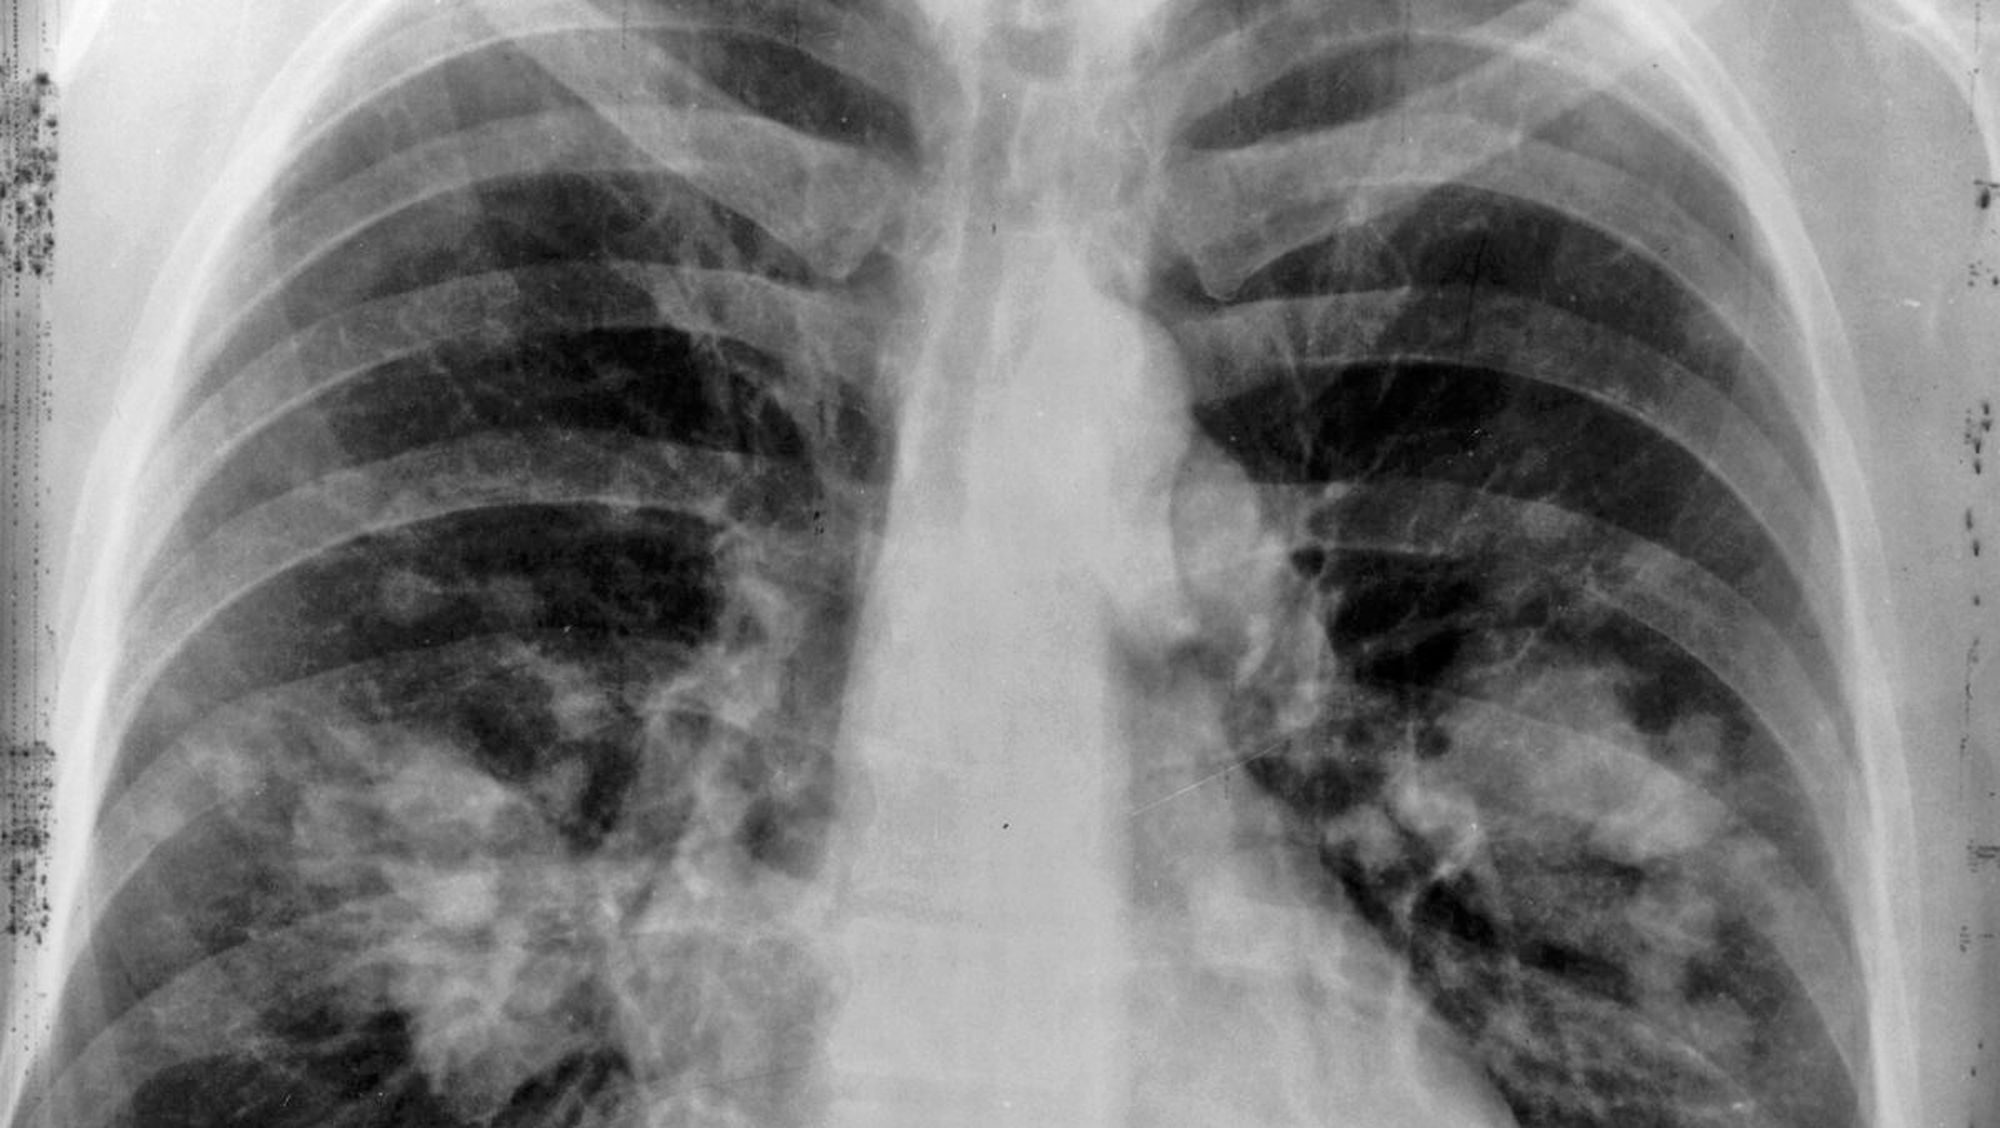

Kadınlarda en çok meme, rahim ve kalın bağırsak kanseri; erkeklerde ise en çok akciğer, prostat, mide ve kalın bağırsak kanserleri görülmektedir. Tüm kanserlerin %16'sı, tüm kanser ölümlerinin %28'i erkeklerde %35, kadınlarda %19 akciğer kanseri nedeniyledir. Akciğer kanseri büyük ölçüde sigara kullanımı ile ilişkilidir; kadınların sigara tüketimindeki artışlar, akciğer kanserlerinin de artmasına neden olmaktadır.

- Solunum sistemi belirtileri Bronş obstrüksiyonu yapan tümörler dispne, pnömoni

- Akciğer parenkiminin yoğun invazyonunda solunum hacmi azalması

- Akciğer kanseri